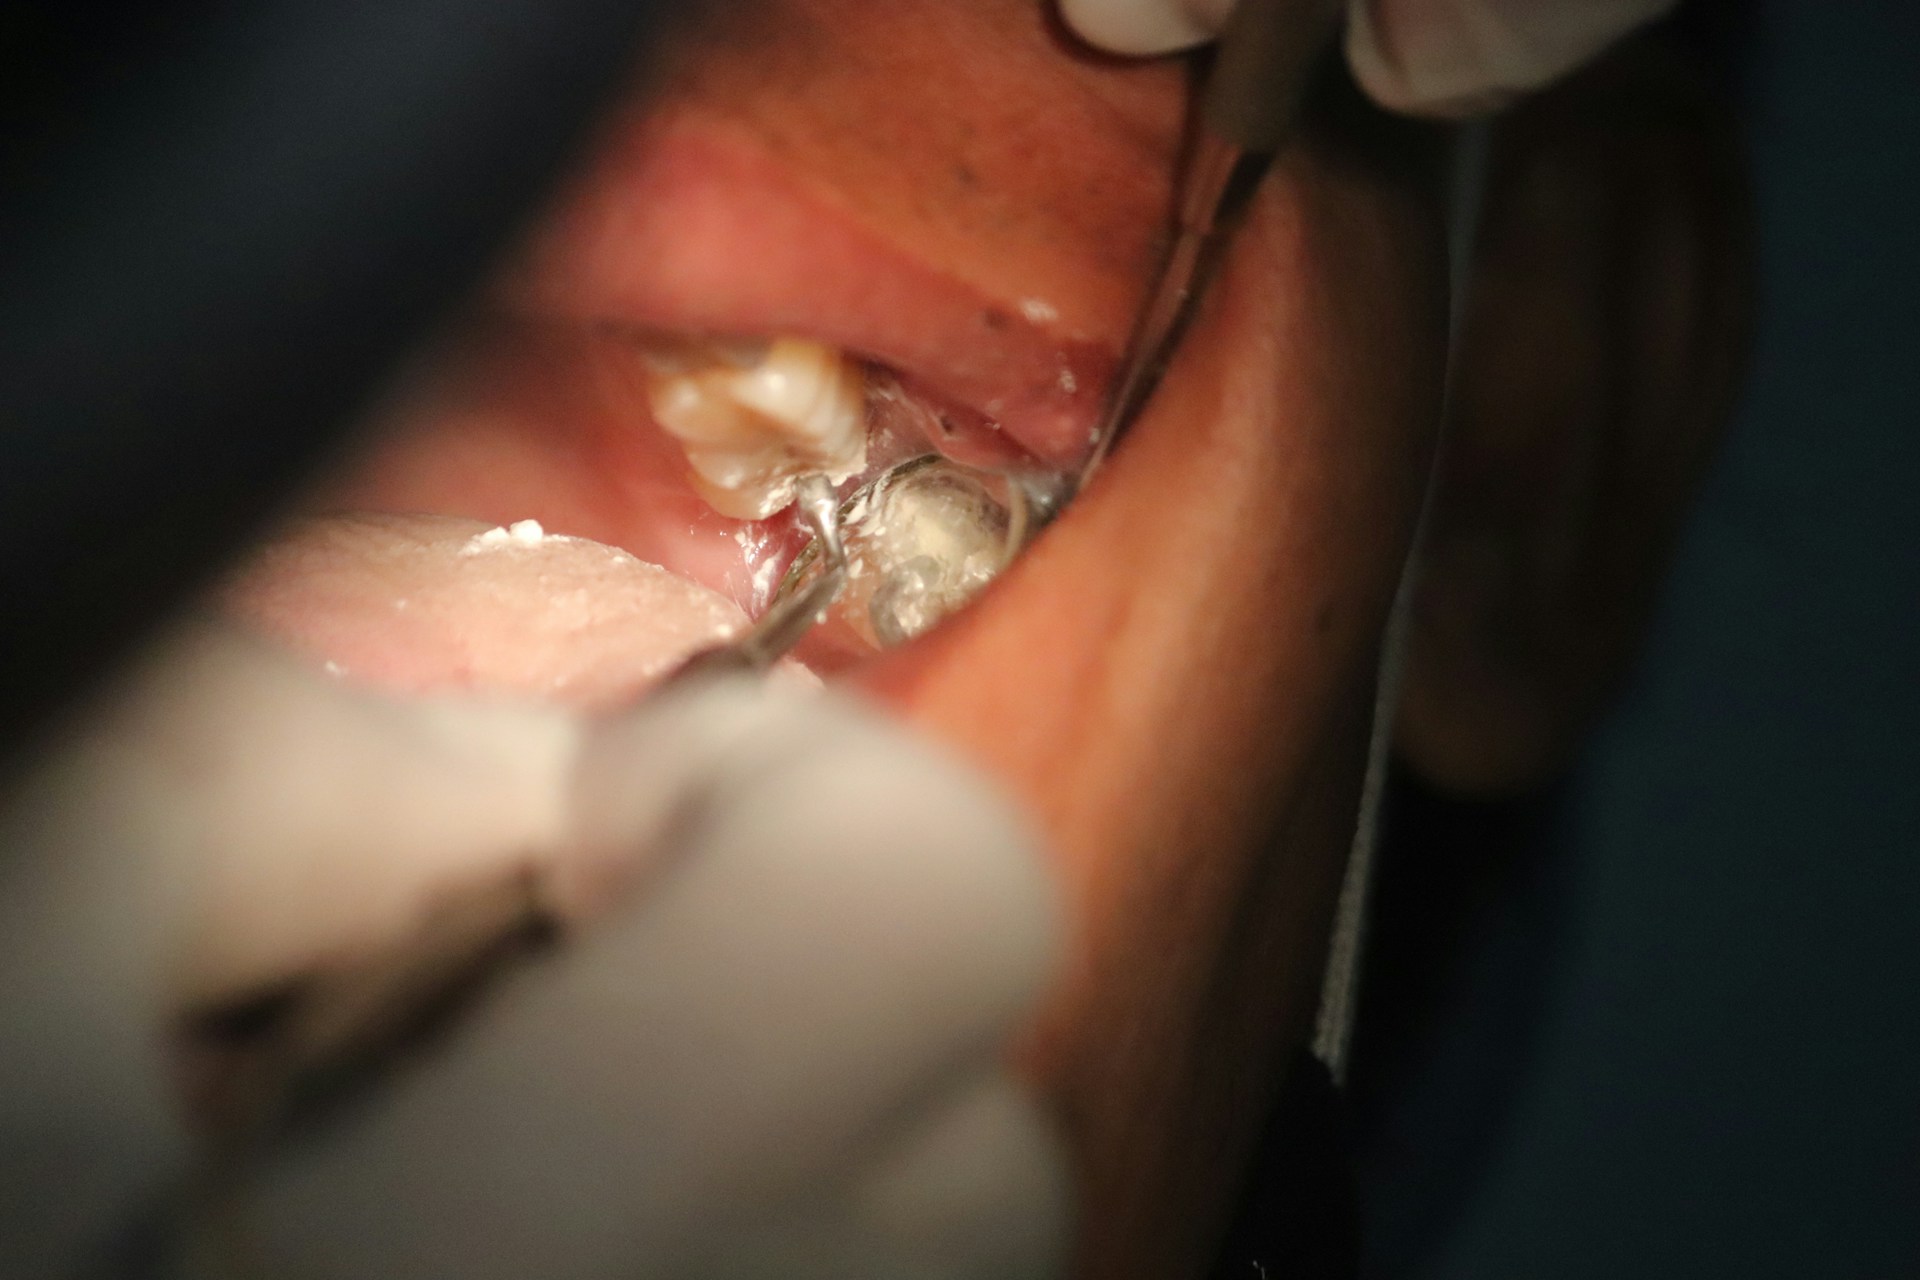

A dental infection or abscess is a serious emergency that requires immediate treatment. Left untreated, infection can spread to the jaw, face, or even bloodstream. At Emergency Dental of Texas, we provide same-day drainage, antibiotics, and definitive treatment to eliminate infection and save your tooth whenever possible.

Immediate drainage of abscess, prescription antibiotics to fight infection

Remove infected pulp to save the tooth and stop pain

If tooth cannot be saved, same-day extraction with sedation available